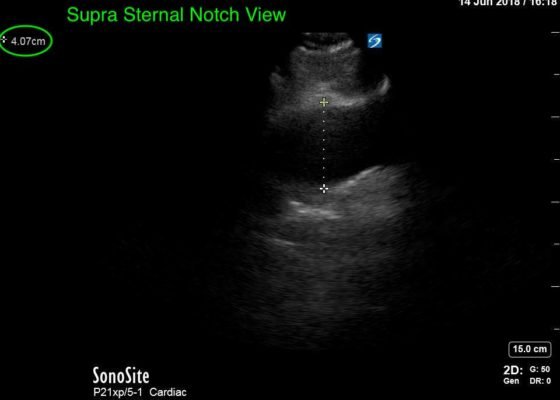

Thoracic Aortic Aneurysm Measured by Point of Care Ultrasound Suprasternal Notch View

DOI: https://doi.org/10.21980/J8Z64VPoint-of-care cardiac echocardiogram demonstrated a dilated ascending aorta (illustrated in red) measuring approximately 4 cm in the parasternal long axis (PLAX). A dilated aortic arch (illustrated in green) also measuring approximately 4 cm was appreciated using the suprasternal notch view (SSNV). A follow-up computed tomography angiogram (CTA) was performed, validating bedside ultrasound measurements.